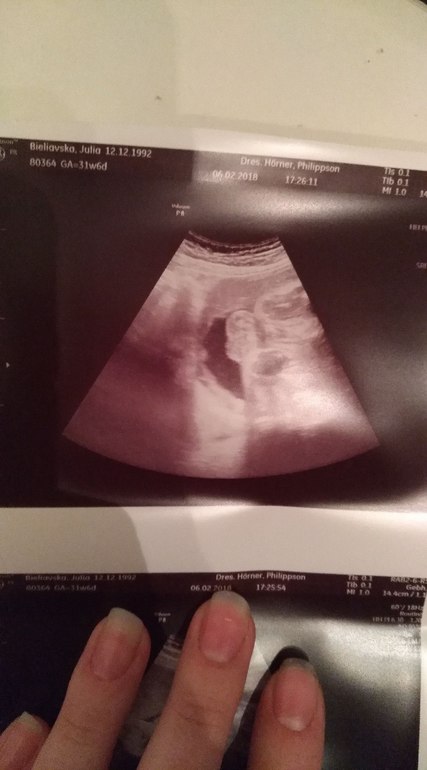

III скрининг, 32 неделя подходит к концу, жидкость в почках

На консультации в ЖК, выбор женской консультации/гинекологаНачнем с веселого! Третий скрининг позади, осталось совсем чуть-чуть ☺️. ИИИИ наша девочка отрастила ЯЙЦА! 🤣. Таким образом Алиса превратилась в Яна! Но это не точно...! 😁 хотя судя по фото.... как думаете? Врач сказала что это яички, но писюнчика так и не нашла.

А теперь о плохом. У малыша в почках обнаружили жидкость. Меня то успокоили что это может ничего особо не значить, но для верности направили к более узкому специалисту в другую клинику. 😐